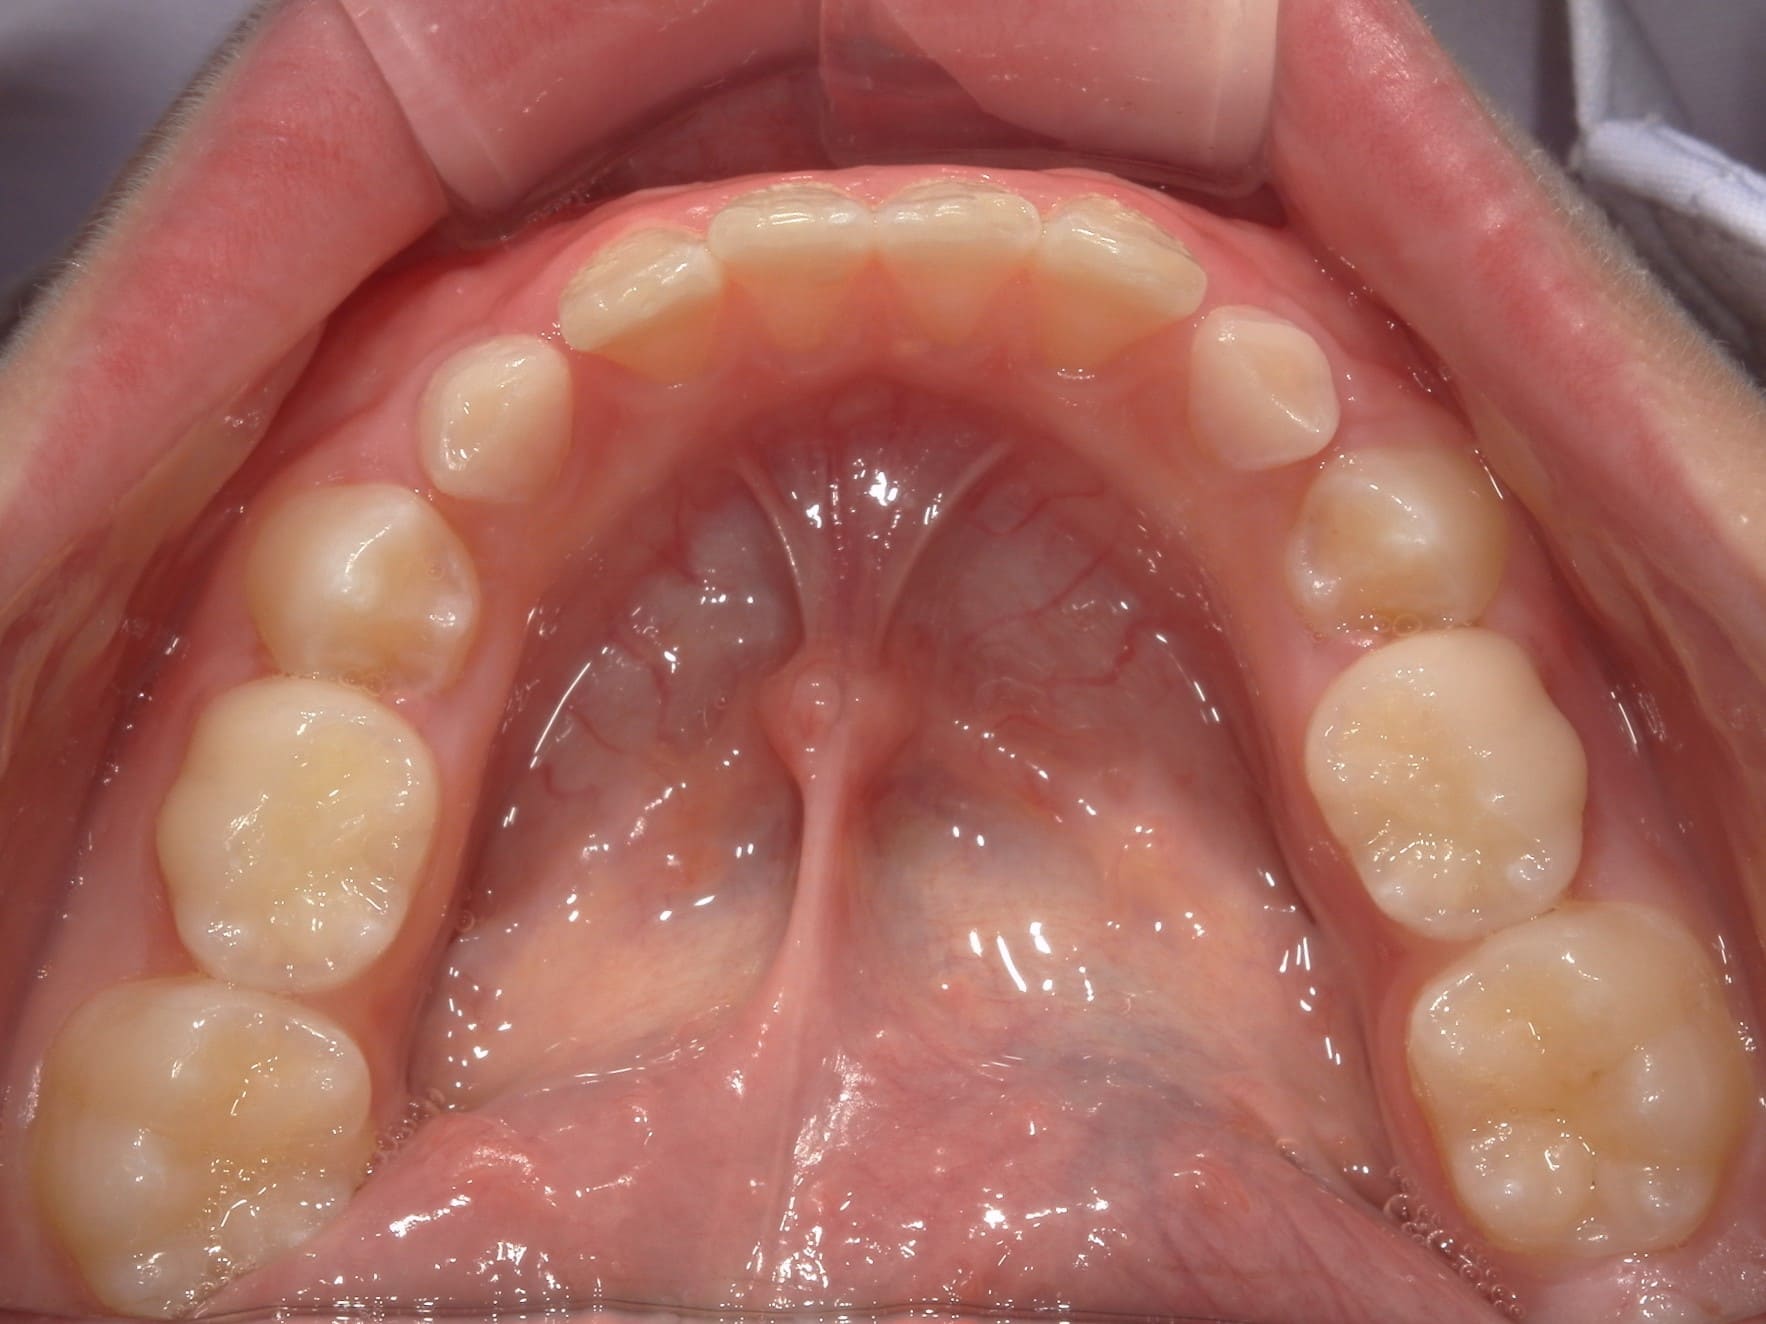

| 年齢・性別 | 8歳3ヶ月の男児 |

|---|---|

| 主訴 | 上顎前歯の位置異常に不安を抱え、歯並びと将来的な咬合状態を整える目的で来院された患者様です。 特に左側の前歯(中切歯および側切歯)の萌出が確認できないことがきっかけとなりました。 |

| 治療期間・回数 | 約5年10ヶ月 |

| 費用 | 460,000円(税別) |